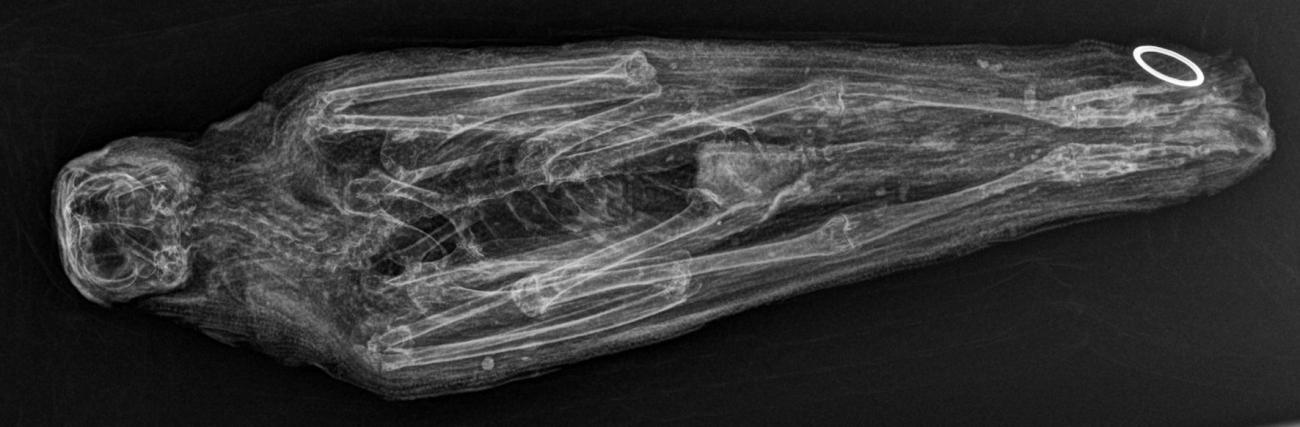

An immature, female Accipiter nisus (See Figure 6) was donated by the Natural History Museum Bird Group, Tring with the purpose of testing the above aims. The specimen named experimental mummy one (EM1) was presented to the Natural History Museum by a member of the public in February 2012 and was dry frozen upon receipt. It was transferred to a dry freezer and kept at -21 °C at the KNH Centre for Biomedical Egyptology, University of Manchester from October-November 2012. Over 72 hours, EM1 was thawed to room temperature and then radiographed (XR and CT) at the Manchester Royal Infirmary2 to ascertain any skeletal damage obtained peri-mortem (See Figure 7). Despite the cause of death being attributed to collision, no trauma was visible and no pathology was evident (See Figure 7). EM1 was then placed in a humidity controlled unit for 48 hours with an average temperature range of 45-48 °C in order to accelerate natural desiccation whilst simultaneously inhibiting bacterial growth (See Figure 8).